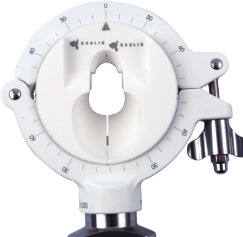

Transrectal

Procedure

KOELIS® 3D ultrasound end-fire probe and accessories enable optimal visualization and targeted interventions via transrectal access.